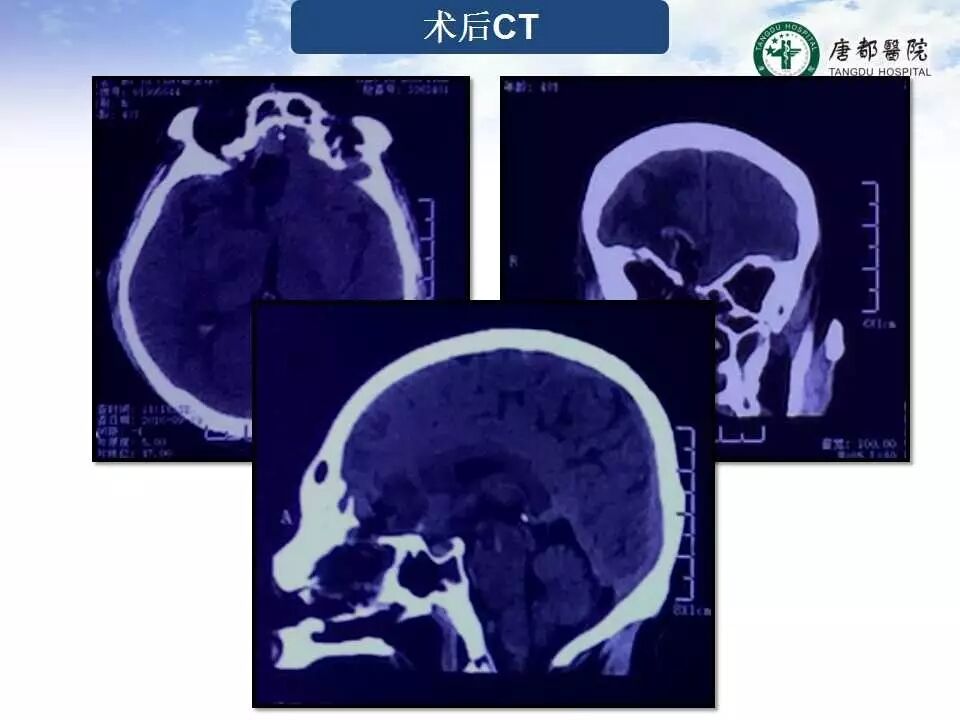

Case 2

长按并识别二维码即可查看该手术视频